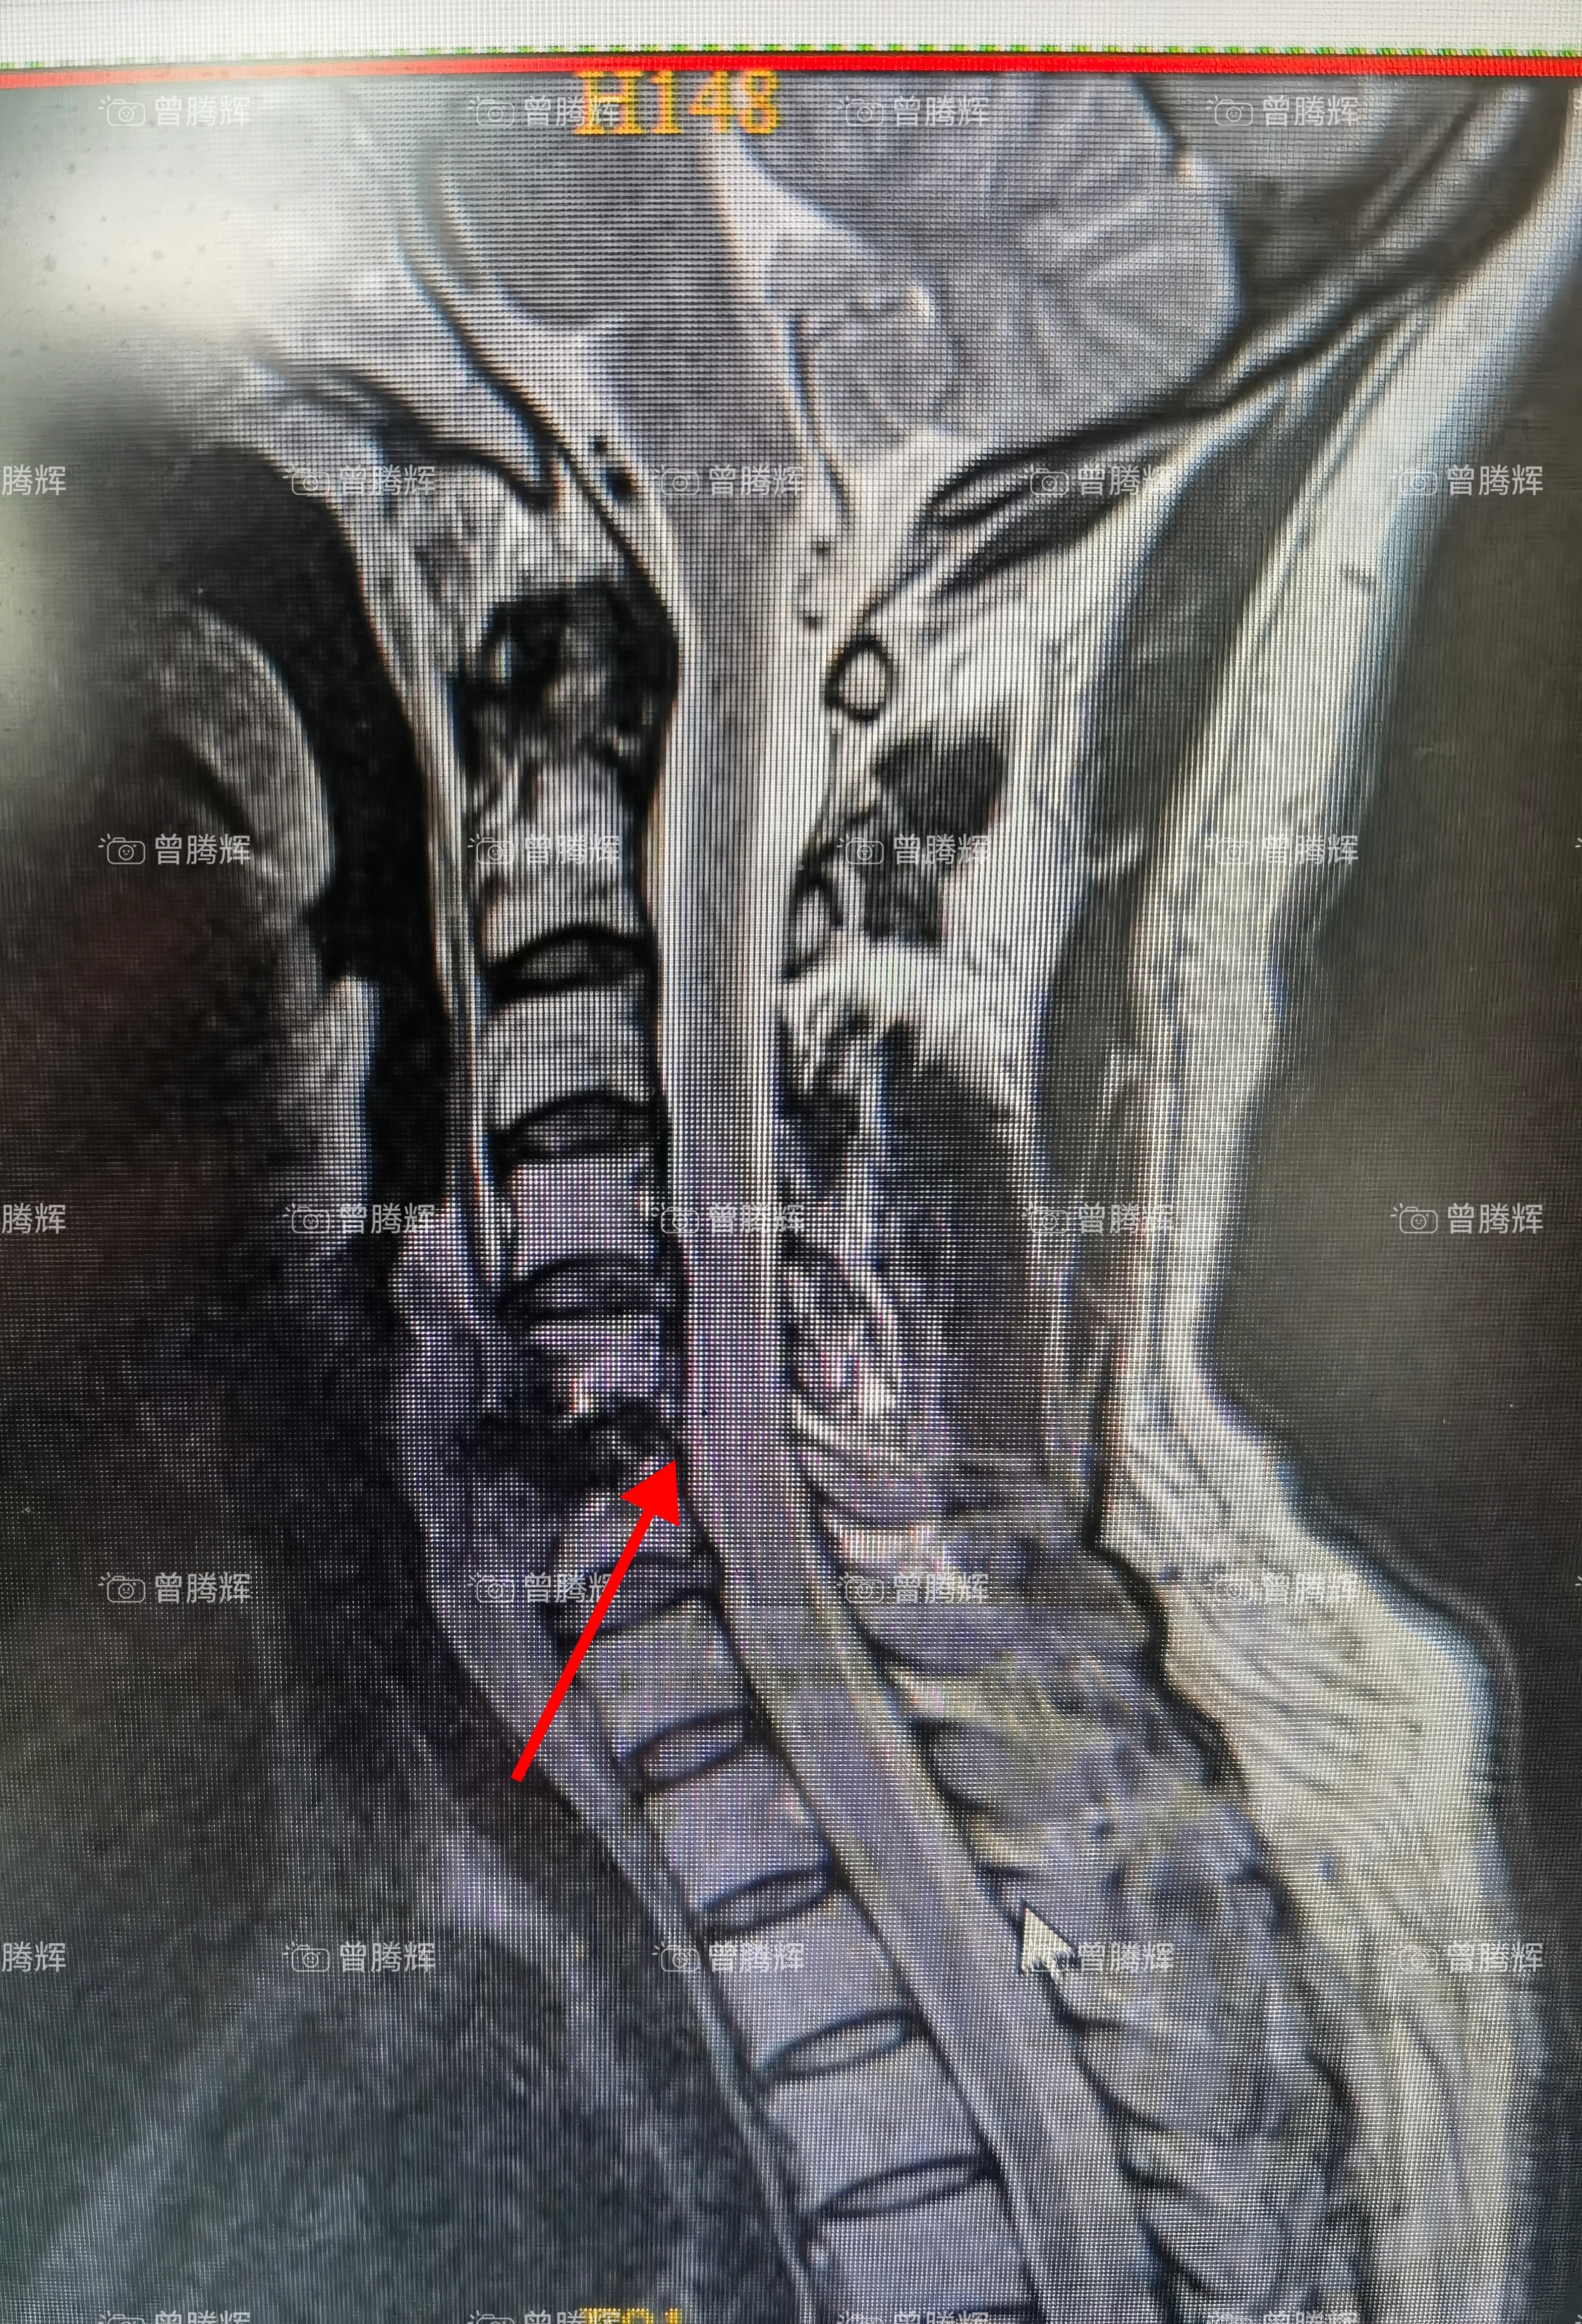

頸椎前路手術

科普:頸椎前路手術是一種天然間隙的微創(chuàng)手術,手術30-60分鐘完成,出血幾毫升,手術后效果很好,立竿見影,術后第1天可以起來,第2天下地行走,精氣神胃口好,看不出做過手術,3-4天可以出院。

曾騰輝醫(yī)生的科普號2023年01月09日300